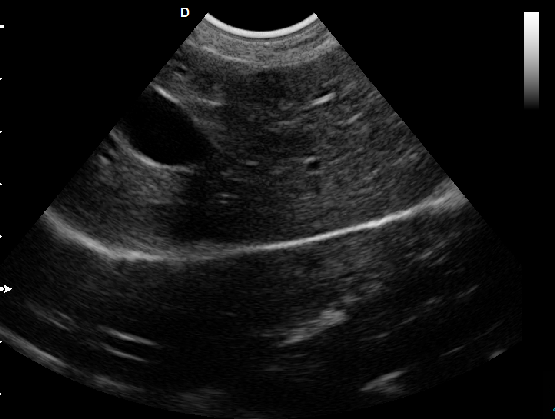

P5-VET獸用彩超機(jī)脊椎檢查圖

脊椎檢查:

脊柱裂的預(yù)防和確診,一般在動(dòng)物懷孕以后定期給動(dòng)物做超聲檢查,通過(guò)超聲、超聲檢查可以早期發(fā)現(xiàn)動(dòng)物胎兒是否合并了脊柱裂或是神經(jīng)管閉合不全。